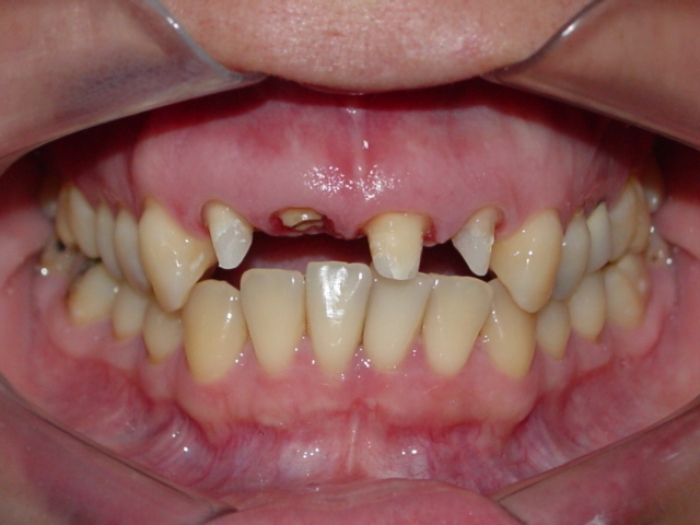

Imagens iniciais com dentes 11 e 25 comprometidos